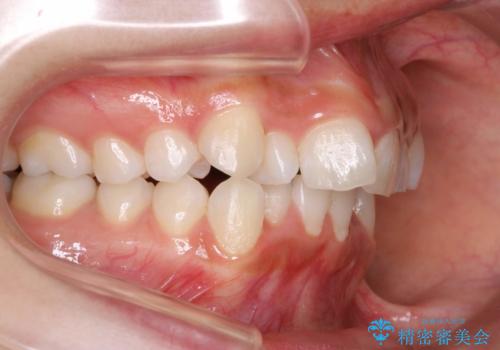

前歯のがたつき・出っ歯 ワイヤーによる抜歯矯正